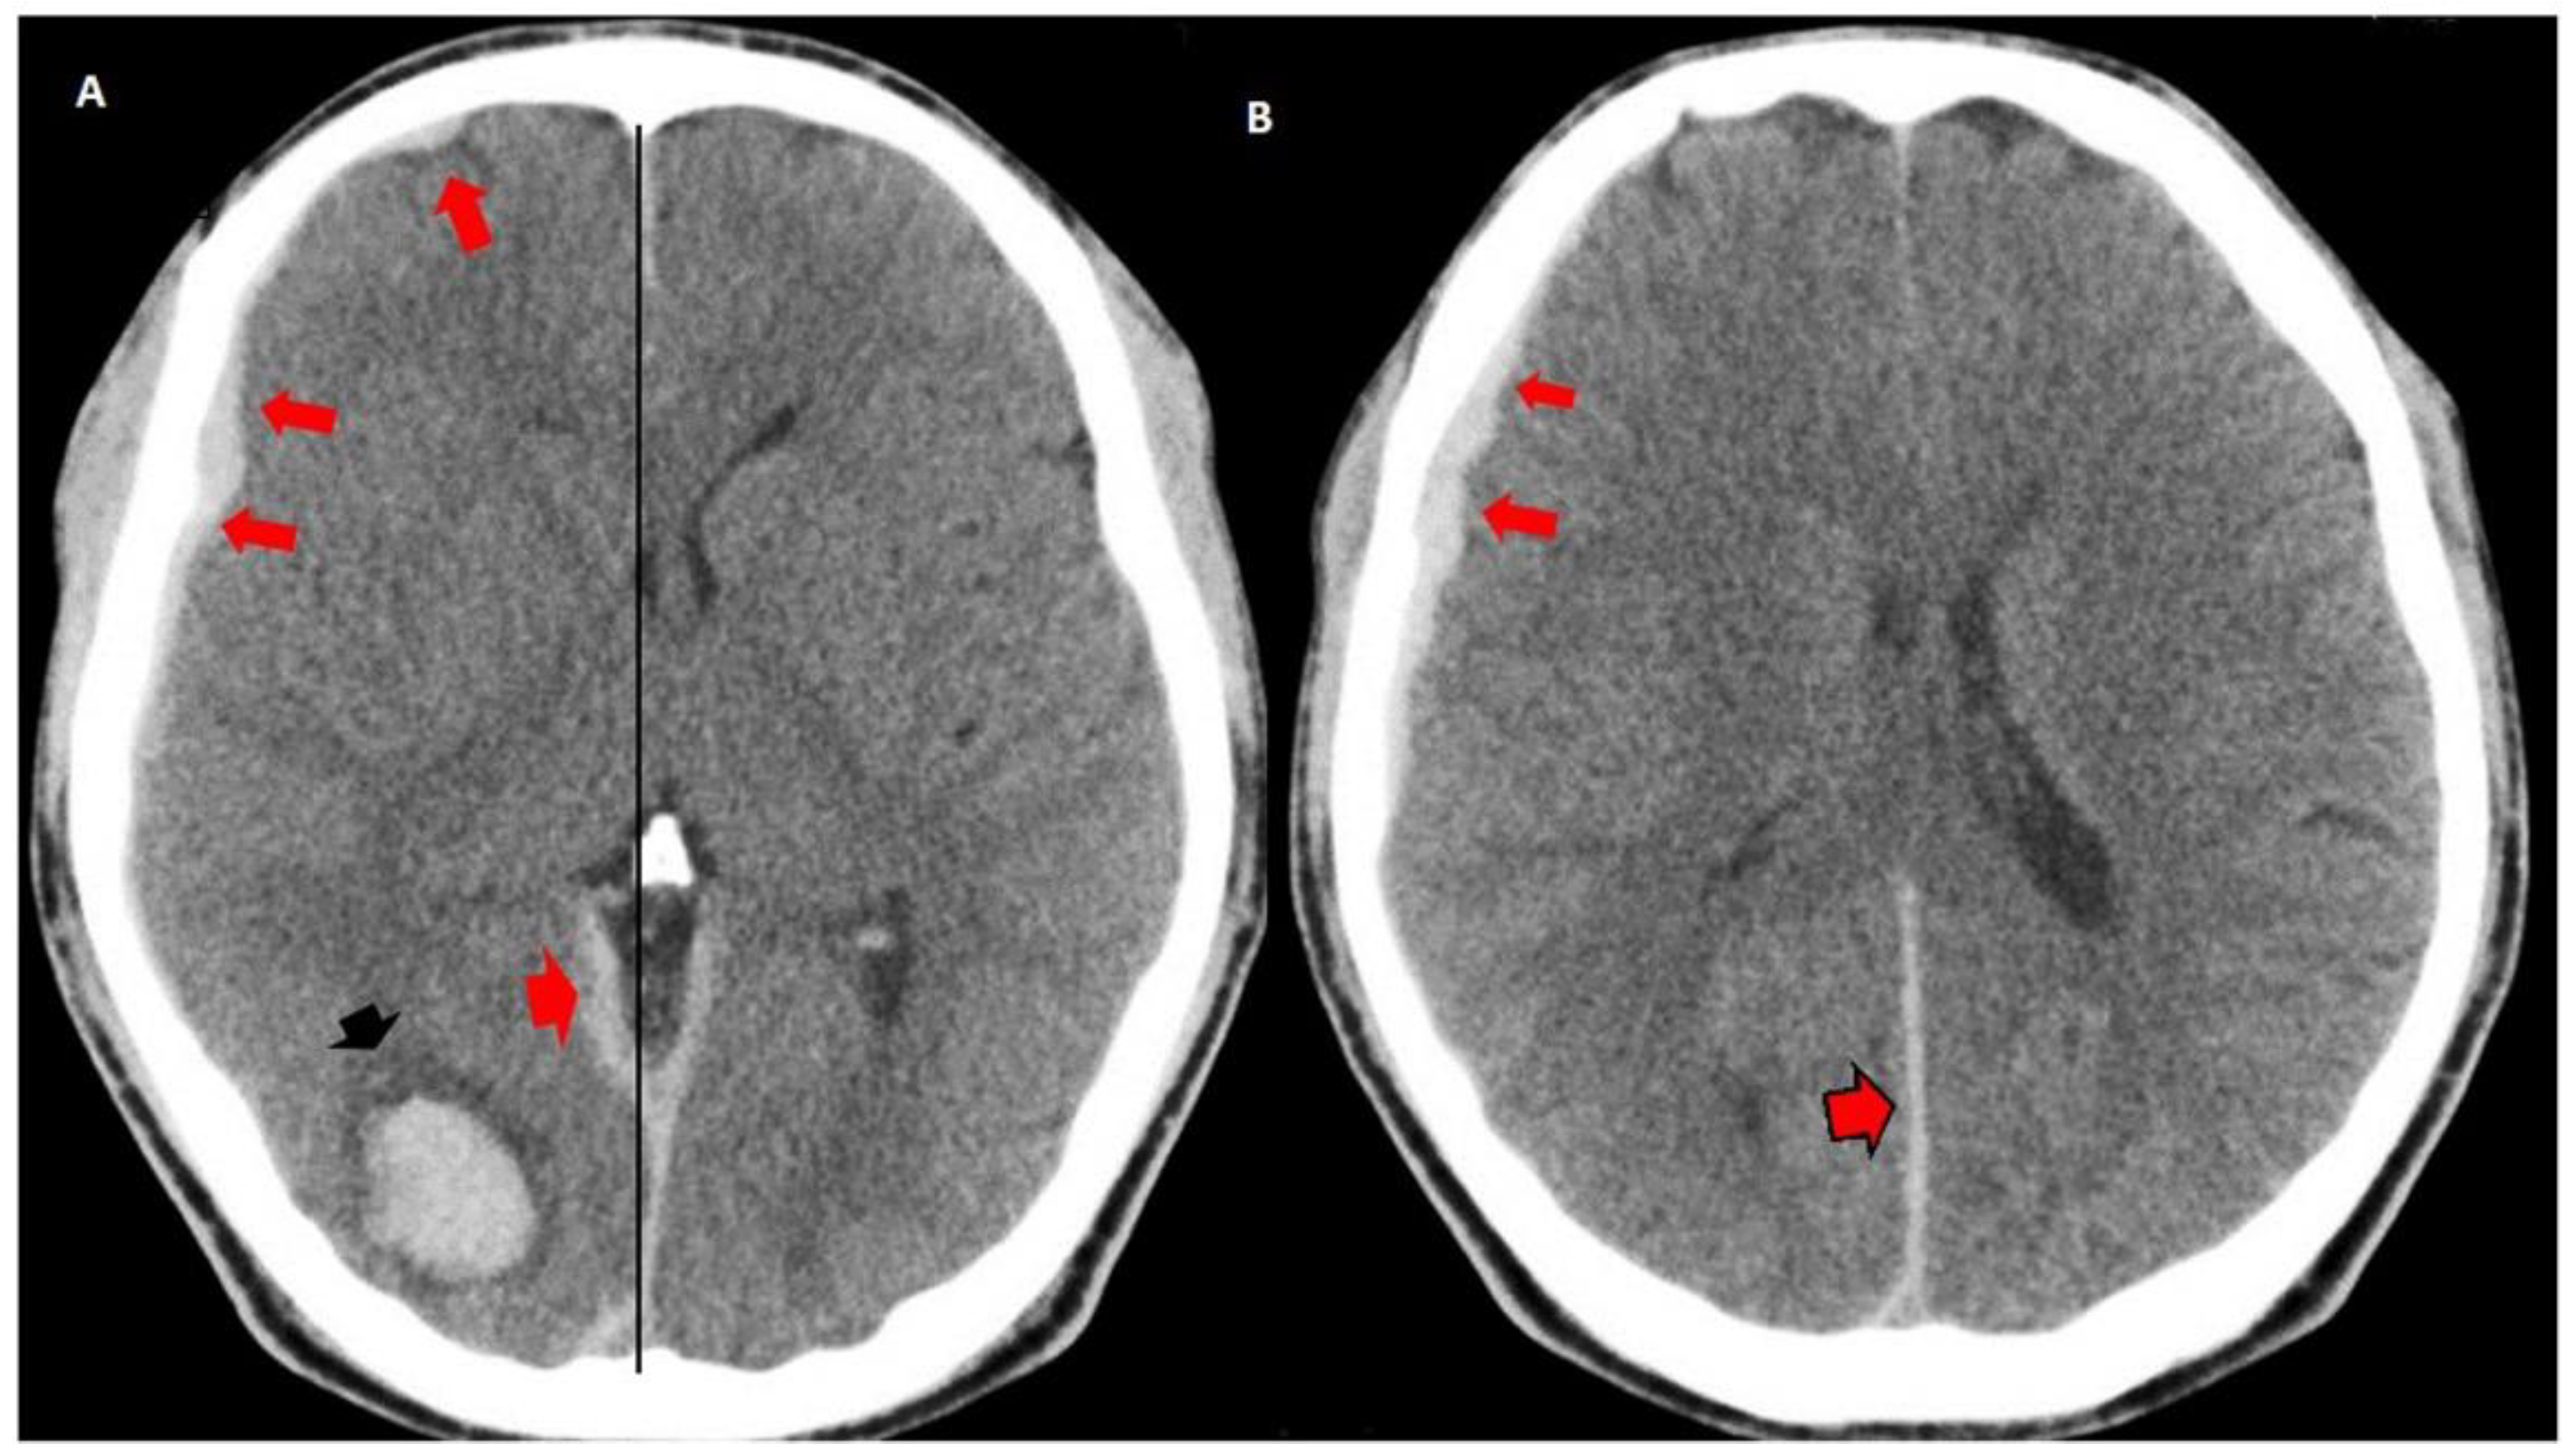

Urgent multislice tomography showed a laminar SDH in the right fronto-parietal region, a posterior interhemispheric fissure at the level of the tentorium, and ipsilateral occipital intracerebral hematoma (2.2 × 2.3 cm in axial section), with a volume of 7 mL. These lesions produced a slight mass effect on the neighboring structures, and the midline was displaced 0.5 cm (Figure 1).

Figure 1.

Simple brain computed tomography (CT): intraparenchymal hematoma in the right occipital region (black arrow head in (A)). Right frontal laminar subdural hematomas: (red arrows in (A,B), subdural hematoma at the tent of the cerebellum (red arrow head) and posterior interhemispheric subdural hematoma in contact with the sickle (red arrow head with black border in (B)). Mild mass effect on the ipsilateral ventricle, effacement of the subarachnoid space. Midline displaced 0.5 cm.